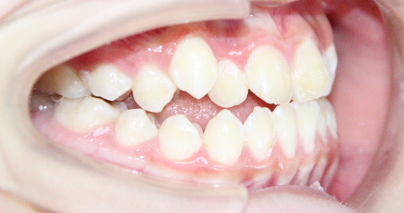

病例2

治疗前